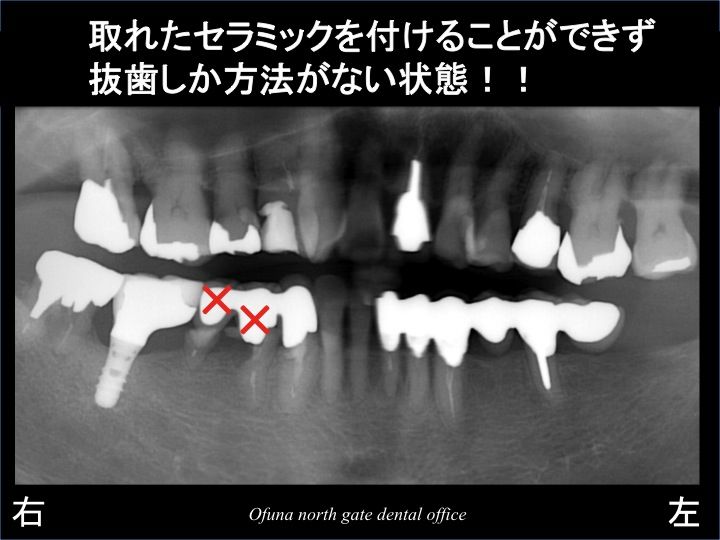

取れた被せ物を見てみると ビックリです。

インプラント治療後(取れた物を再度被せ物を付けた後)とは違っていました。

なんと他の歯科医院で 取れた3歯を抜歯しないで新しくセラミックで治療がされていたのです。

そのセラミックを行った歯が取れたというのです。

当たり前です。

抜歯しか治療法がないような状態の歯を 無理矢理セラミックで治療しているからです。

また、取れないように3歯分を連結してありました。

連結すれば それだけ 取れにくいのは確かだからです。

しかし、3歯分を連結した被せ物は、完成から数ヶ月も保たずに再度取れてしまったのです。

ちなみに このセラミックの費用は40万円以上したそうです。

治療期間より、短く取れてしまったのです。

当然と言えば、当然の結果です。

始めからダメな歯を 無理にセラミックにしたのですから…

ダメになった部分を拡大してみましょう!

見る人が見れば明らかに分かるような 悪い状態です。